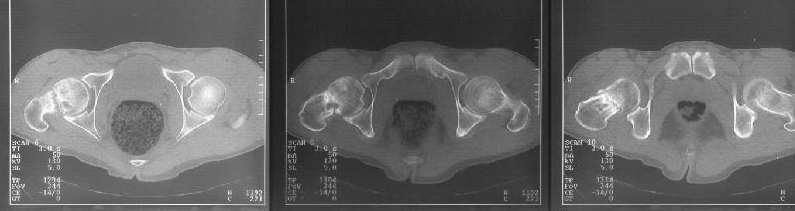

A male (32 y.o, 175 cm, 65 kg) after a car accident 1 year ago sustained a femoral neck fracture. The fracture was fixed elsewhere by cancellous screws. He noted telescoping of the screws four month later. Recently the screws have been removed. Walks with cane and marks hip pain. Xrays and CT (see attachment) demonstrate pseudarthrosis of the neck.

In a 32 year old male with a femoral neck nonunion, his best option is probably a valgus producing intertrochanteric osteotomy with blade plate fixation. In the preoperative planning stage, neutral rotation (patella up) 100% films of both hips are necessary. The AP film enclosed is with significant external rotation given the appearance of the lesser trochanter. It doesn't appear that there is significant retroversion based on the CT scan. Depending upon what his neck shaft angle is compared with his normal side, a better recommendation of the degree of osteotomy can be made. Predictable results (ie union) can be obtained without trying to reproduce a fracture angle of 25 degrees. That is, a 20 or 30 degree valgus producing intertrochanteric osteotomy with a 110 degree or 120 degree blade plate, respectively, should give a reliable result. According to the preoperartive plan with comparison to the contralateral hip in the same rotation, the lateralization of the shaft can be accomplished to help minimize proximal deformity and lateral compartment overload of the knee (theoretically). Length can be simultaneously gained as well.

Most 32 year olds should be treated with osteotomy. However, I am concerned that the x-rays imply some early avascular necrosis (there is some lucency and irregularity in the superior femoral head), and I would at least obtain an MRI to assess its extent if it is present. This can give an idea as to prognosis. If AVN is present, I would consider adding either a vascularized fibula to my osteotomy procedure or a vascularized quadratus femoris bone block transfer to try to increase the chance of healing. If there is extensive whole head involvement of AVN, then I might even consider hip replacement even at this age (although I'd again prefer to do osteotomy), because hip replacement after osteotomy with the deformed femoral canal can be much more technically difficult and if failure appears inevitable, why make the next surgery harder? Again, first choice is osteotomy, but I'd like to know the femoral head's status before surgery. (In the litiginous USA, it might also be useful to know that the AVN was present before the osteotomy so that when it develops postop, the osteotomy surgery isn't blamed.)